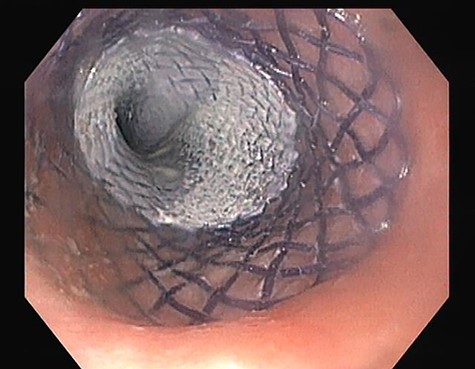

At the 24-month follow-up, an upper endoscopy confirmed integrity of the stomach pouch and GJA without any GGF (see Fig. 10). Thirty-six months after surgical treatment of the GGF, the patient remains asymptomatic and has a stable BMI.

Esophagogastroduodenoscopy image showing a normal gastric pouch with only one orifice corresponding to the gastro-jejunal anastomosis (arrow).